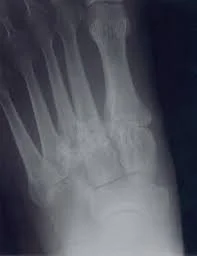

Imaging is essential for diagnosis. Weight-bearing X-rays typically demonstrate joint space narrowing, bone spurs, sclerosis, or collapse of the arch. CT scans may be used to better define the extent of arthritis and assist with surgical planning, while MRI can evaluate associated soft-tissue pathology in select cases.